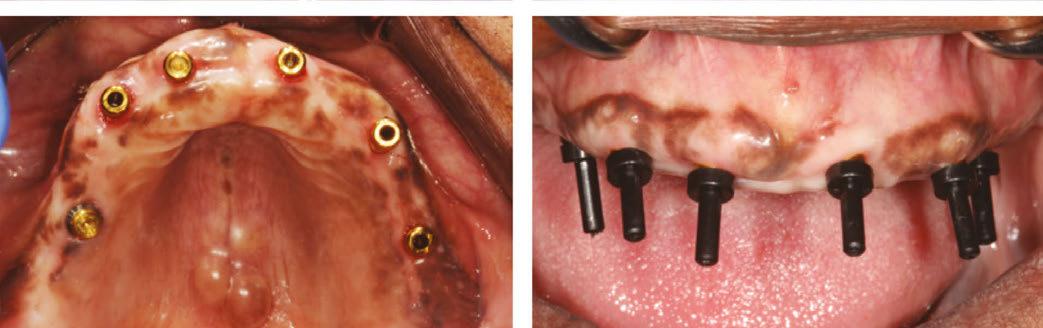

An 80-year-old male with a relatively clean medical history was referred for full-arch immediately loaded maxillary implant treatment. The patient had been previously treated with maxillary dental implants in a traditional All-on-X approach. The referring clinician noted that the patient’s bone was extremely “soft” and that insertion torque for most of the implants was very low. Although these implants were not immediately loaded, they ultimately failed and created large oroantral communications. While the communications were ultimately closed, extremely large

Figure 7 (left): CBCT slice (sagittal view) for vertical measurement from subnasal bone to prelacrimal bone engagement point. Figure 8 (middle): Panoramic radiograph of patient with history of failed All-on-X treatment, oroantral fistulae, and thickened Schneiderian membranes. Figure 9 (right): Intrasurgical photo of transnasal dental implant traversing the nasal cavity and engaging the base of the inferior concha

defects resulted in the floor and walls of the maxillary sinuses (Figure 8). CBCT analysis revealed a significantly thickened left Schneiderian membrane and occluded osteomeatal complex. The patient was referred to ENT for a Functional Endoscopic Sinus Surgery (FESS) procedure. Upon healing, a new CBCT was taken and evaluated for potential treatment.

Due to the atrophic nature of the maxilla, treatment following the PATZi protocol was planned.6,17,20 CBCT evaluation revealed pterygomaxillary bone appropriate for pterygoid implants allowing for posterior arch support and cantilever elimination. The zygomas were of adequate height and width to accommodate multiple zygomatic implant fixtures bilaterally. PLACATE guidelines were used to evaluate the patient for potential treatment with transnasal implants. With Simmen 3 nasolacrimal canal classification, ≥ 3 mm of prelacrimal bone, ≥2 mm subnasal bone, and ≤ 25 mm to the Z-point, the patient satisfied all PLACATE parameters. Accordingly, a treatment plan of bilateral pterygoid, single zygomatic, and transnasal implants was agreed upon.

Following the induction of general anesthesia, extraoral and intraoral local anesthesia was applied. To avoid exposing the large subantral bony defects, mini-flaps were elevated at the pterygoid landing areas to expose the hamular notch. The pterygoid fossa was identified via probing, and pterygoid implant placement ensued. Following the PATZi protocol, bilateral pterygoid implants were placed first and both achieved insertion torque between 45+ Ncm.

Following PATZi, anterior support was sought next. As such, the nasal mucosa was elevated to expose the floor of the nasal cavity and the bone of the inferior conchae. A pair of 25 mm transnasal implants were placed, and each achieved high insertion torque of 45+ Ncm (Figures 9-11). Continuing with the PATZi protocol and treatment plan, 42.5 mm long zygomatic implants were placed in both zygomas. The zygomatic implants were placed using an extrasinus approach and both achieved insertion torque of 45+Ncm. Buccal fat pedicles were advanced bilaterally to cover extrasinus portions of the zygomatic implants, and flap closure was achieved with 4-0 chromic gut suture. The patient was immediately temporized with a screw-retained transitional bridge (Figure 12), and a final zirconia restoration was delivered after 8 months of healing (Figure 13).